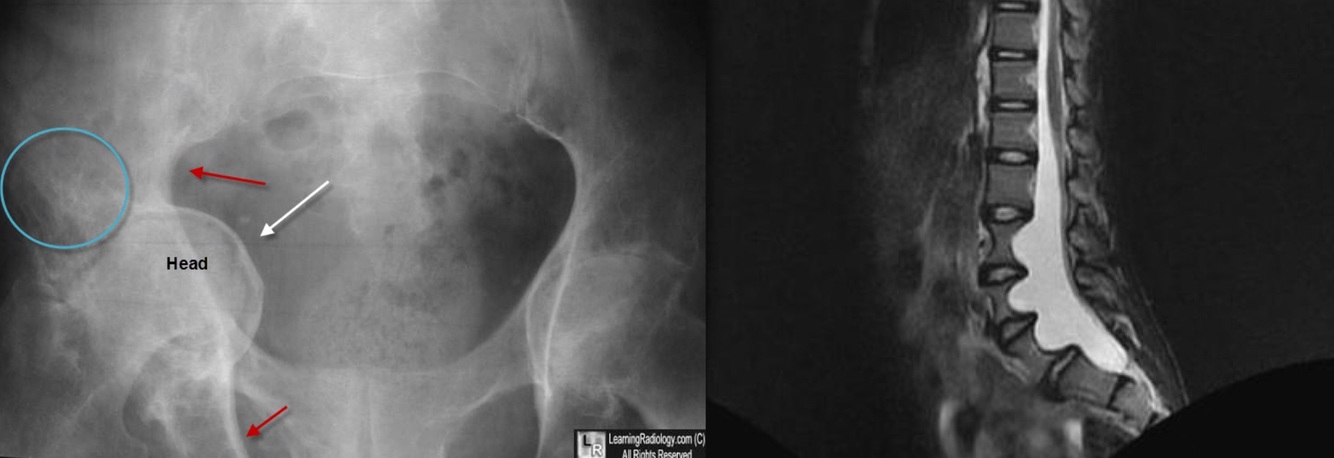

12

Q

[Gen/CT]

Name of anomaly?

Name of syndrome?

Hyperflexibility, MVP, Increased arm to height

A

Protrusio actabuli

Marfan syndrome